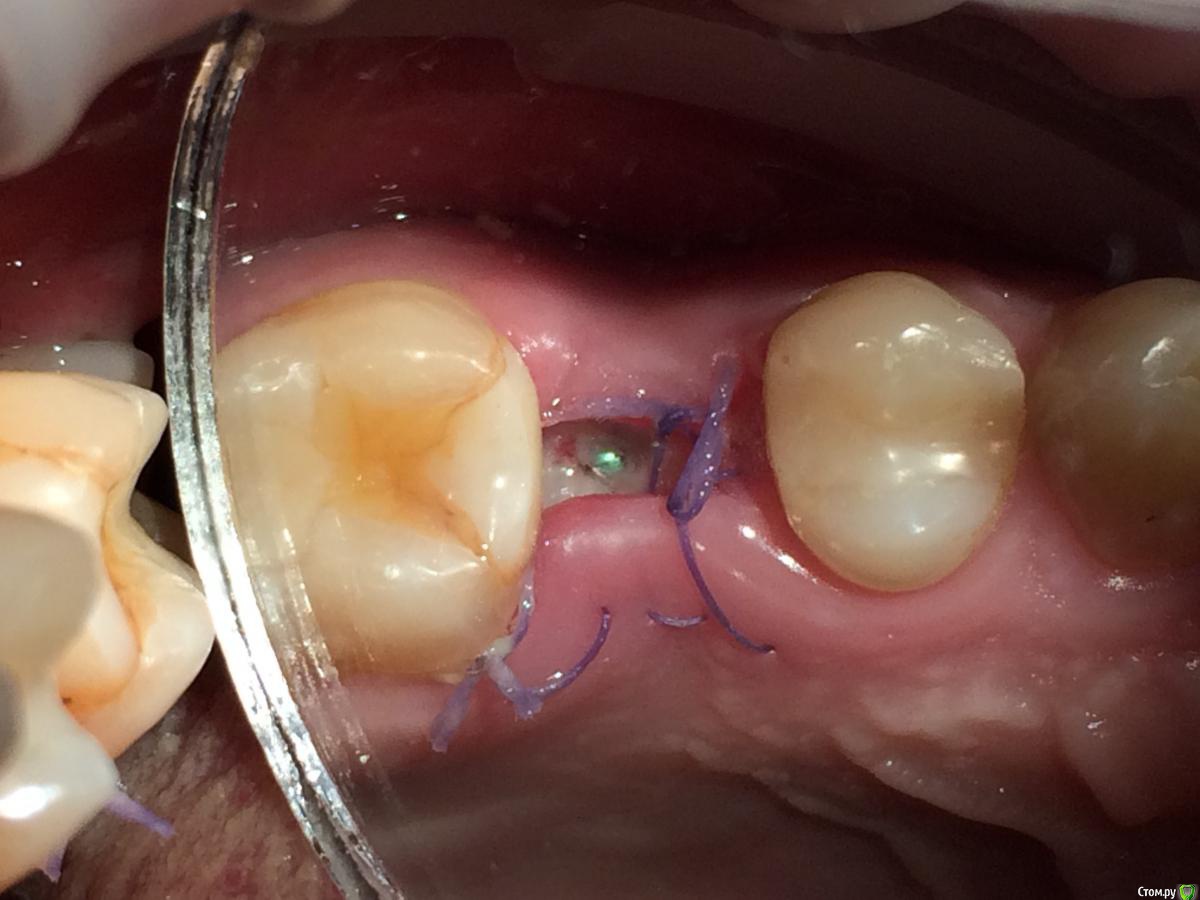

Graffwoman Опубликовано 25 февраля, 2018 Поделиться Опубликовано 25 февраля, 2018 Здравствуйте,уважаемые коллеги! Помогите кто-чем может)). Надо - очень срочно....(((8 дней назад установлен имплантат Osstem. Жалобы на сохраняющуюся одинаковую со дня вмешательства тупую,неприятную,ноющую боль в области проекции верхушки имплантата. Появляется примерно через 3 часа после пробуждения. Ротовые ванночки мирамистином и пьет нимесил 2 раза в сутки.Температура-36,4 *. Перед установкой хирург заметил небольшую полоску гноя из кармашка 26 (а,может,размягченые остатки пищи из под нависающего края пломбы 26,он был расположен под десной ,но похоже ,что гной). Операцию по установке откладывать не стали,пациент пополоскал рот и бетадином было обработано операционное поле.Четко понимаю,что отошли от протокола : не назначили антибиотикотерапию и осмотр на 3-й день произведен не был-так получилось..В анамнезе 3 года назад -двусторонний гайморит.Сейчас выделения из носа прозрачные только утром незначительное количество-то справа ,то слева. Когда появились не очень помнит,возможно до имплантации Антибиотики начал пить на 5- сутки после операции. При осмотре на 8-й день пальпация щеки и слизистой по своду переходной складки болезненна в одной точке чуть дистальнее проекции верхушки имплантата..Шов не состоятелен. В ране гнилостный запах .Обработали рану,хлоргексидином.На прицельном -пока спокойно.Это воспаление в мягких тканях без резорбции в периимплантной области ?Надо удалить имплантат , пока не поздно?Надежды никакой ? Посоветуйте,что делать,пожалуйста .С благодарностью надеюсь на ответ. Ссылка на комментарий

Дмитрий Л. Опубликовано 25 февраля, 2018 Поделиться Опубликовано 25 февраля, 2018 Удалите осторожно швы, они не нужны уже. Каждый день пускай приходит к вам промывать, дома пусть полощит чем-то раз 5 в день, можно гель с а/б, защитную каппу из термопресса для приема пищи. Думаю туго зашили. Мукозит. Ссылка на комментарий

Irouil Опубликовано 25 февраля, 2018 Поделиться Опубликовано 25 февраля, 2018 Выкрутить заглушку, Метрогилом все залить, поставить формик самый тонкий и короткий, но чтобы не уходил под десну, сделать разрез по переходной складке на всякий случай, дренаж, туда тоже Метрогила, естественно при всех кручениях стараемся чувствовать торк и не выкрутить имплантат. Затем на осмотрах продолжаем мыть хлором и заливать Метрогил в десневую борозду пока не успокоится. Если успокоится. Выделения с двух сторон из носа если то я не вижу причем тут имплантат. Ссылка на комментарий

Graffwoman Опубликовано 25 февраля, 2018 Автор Поделиться Опубликовано 25 февраля, 2018 Выкрутить заглушку, Метрогилом все залить, поставить формик самый тонкий и короткий, но чтобы не уходил под десну, сделать разрез по переходной складке на всякий случай, дренаж, туда тоже Метрогила, естественно при всех кручениях стараемся чувствовать торк и не выкрутить имплантат. Затем на осмотрах продолжаем мыть хлором и заливать Метрогил в десневую борозду пока не успокоится. Если успокоится. Выделения с двух сторон из носа если то я не вижу причем тут имплантат.Спасибо огромное всем . Написала про выделения из носа для полноты инфы,тк в гайморовой утолщение слизистой кое-где до 10 мм. Прием только завтра. На дом назначила полоскания мирамистином через каждые час -полтора и смазывание -закладывание геля метрогил дента."Если успокоится "- ориентировочный срок ?Если нет -убираем имплантат ? Ссылка на комментарий